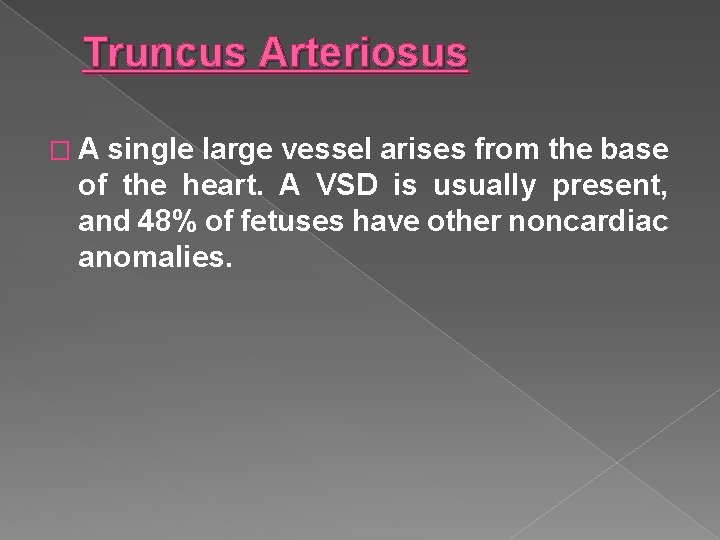

Truncus Arteriosus � A single large vessel arises from the base of the heart. A VSD is usually present, and 48% of fetuses have other noncardiac anomalies.